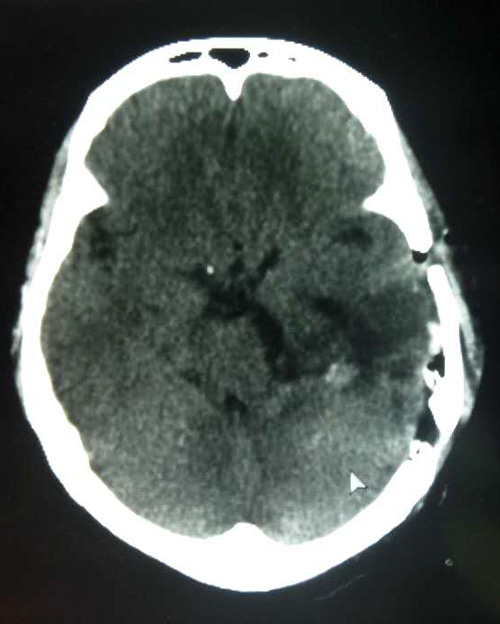

手术台上,全麻状态下的患者安稳地沉睡着。沈建康教授眼前的肿瘤质地柔软,呈灰褐色。肿瘤已压迫“生命中枢”脑干,所幸与脑供血动脉黏连并不紧密。沈建康教授凭借娴熟的手术技艺,在医院先进的高倍显微镜下精雕细刻,轻轻牵拉、小心剥离,历时约5个小时,分块将肿瘤切除。术后通过CT复查,已不见肿瘤踪迹,手术取得了成功。

▲患者术后CT已不见肿瘤踪影